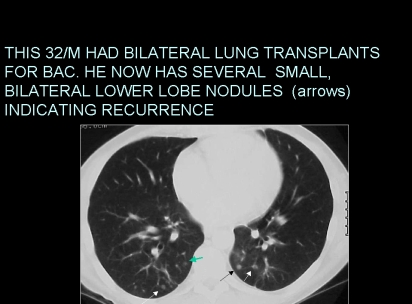

Slide 31